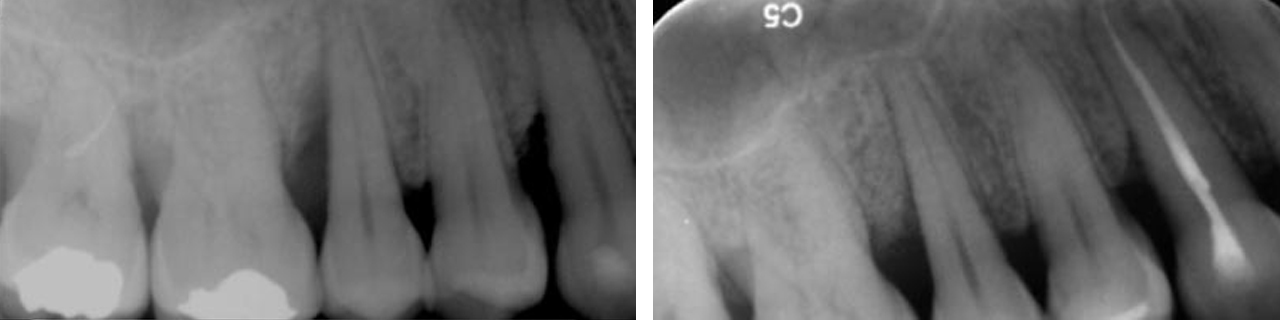

Regeneración

Regeneración del hueso alrededor de los dientes.